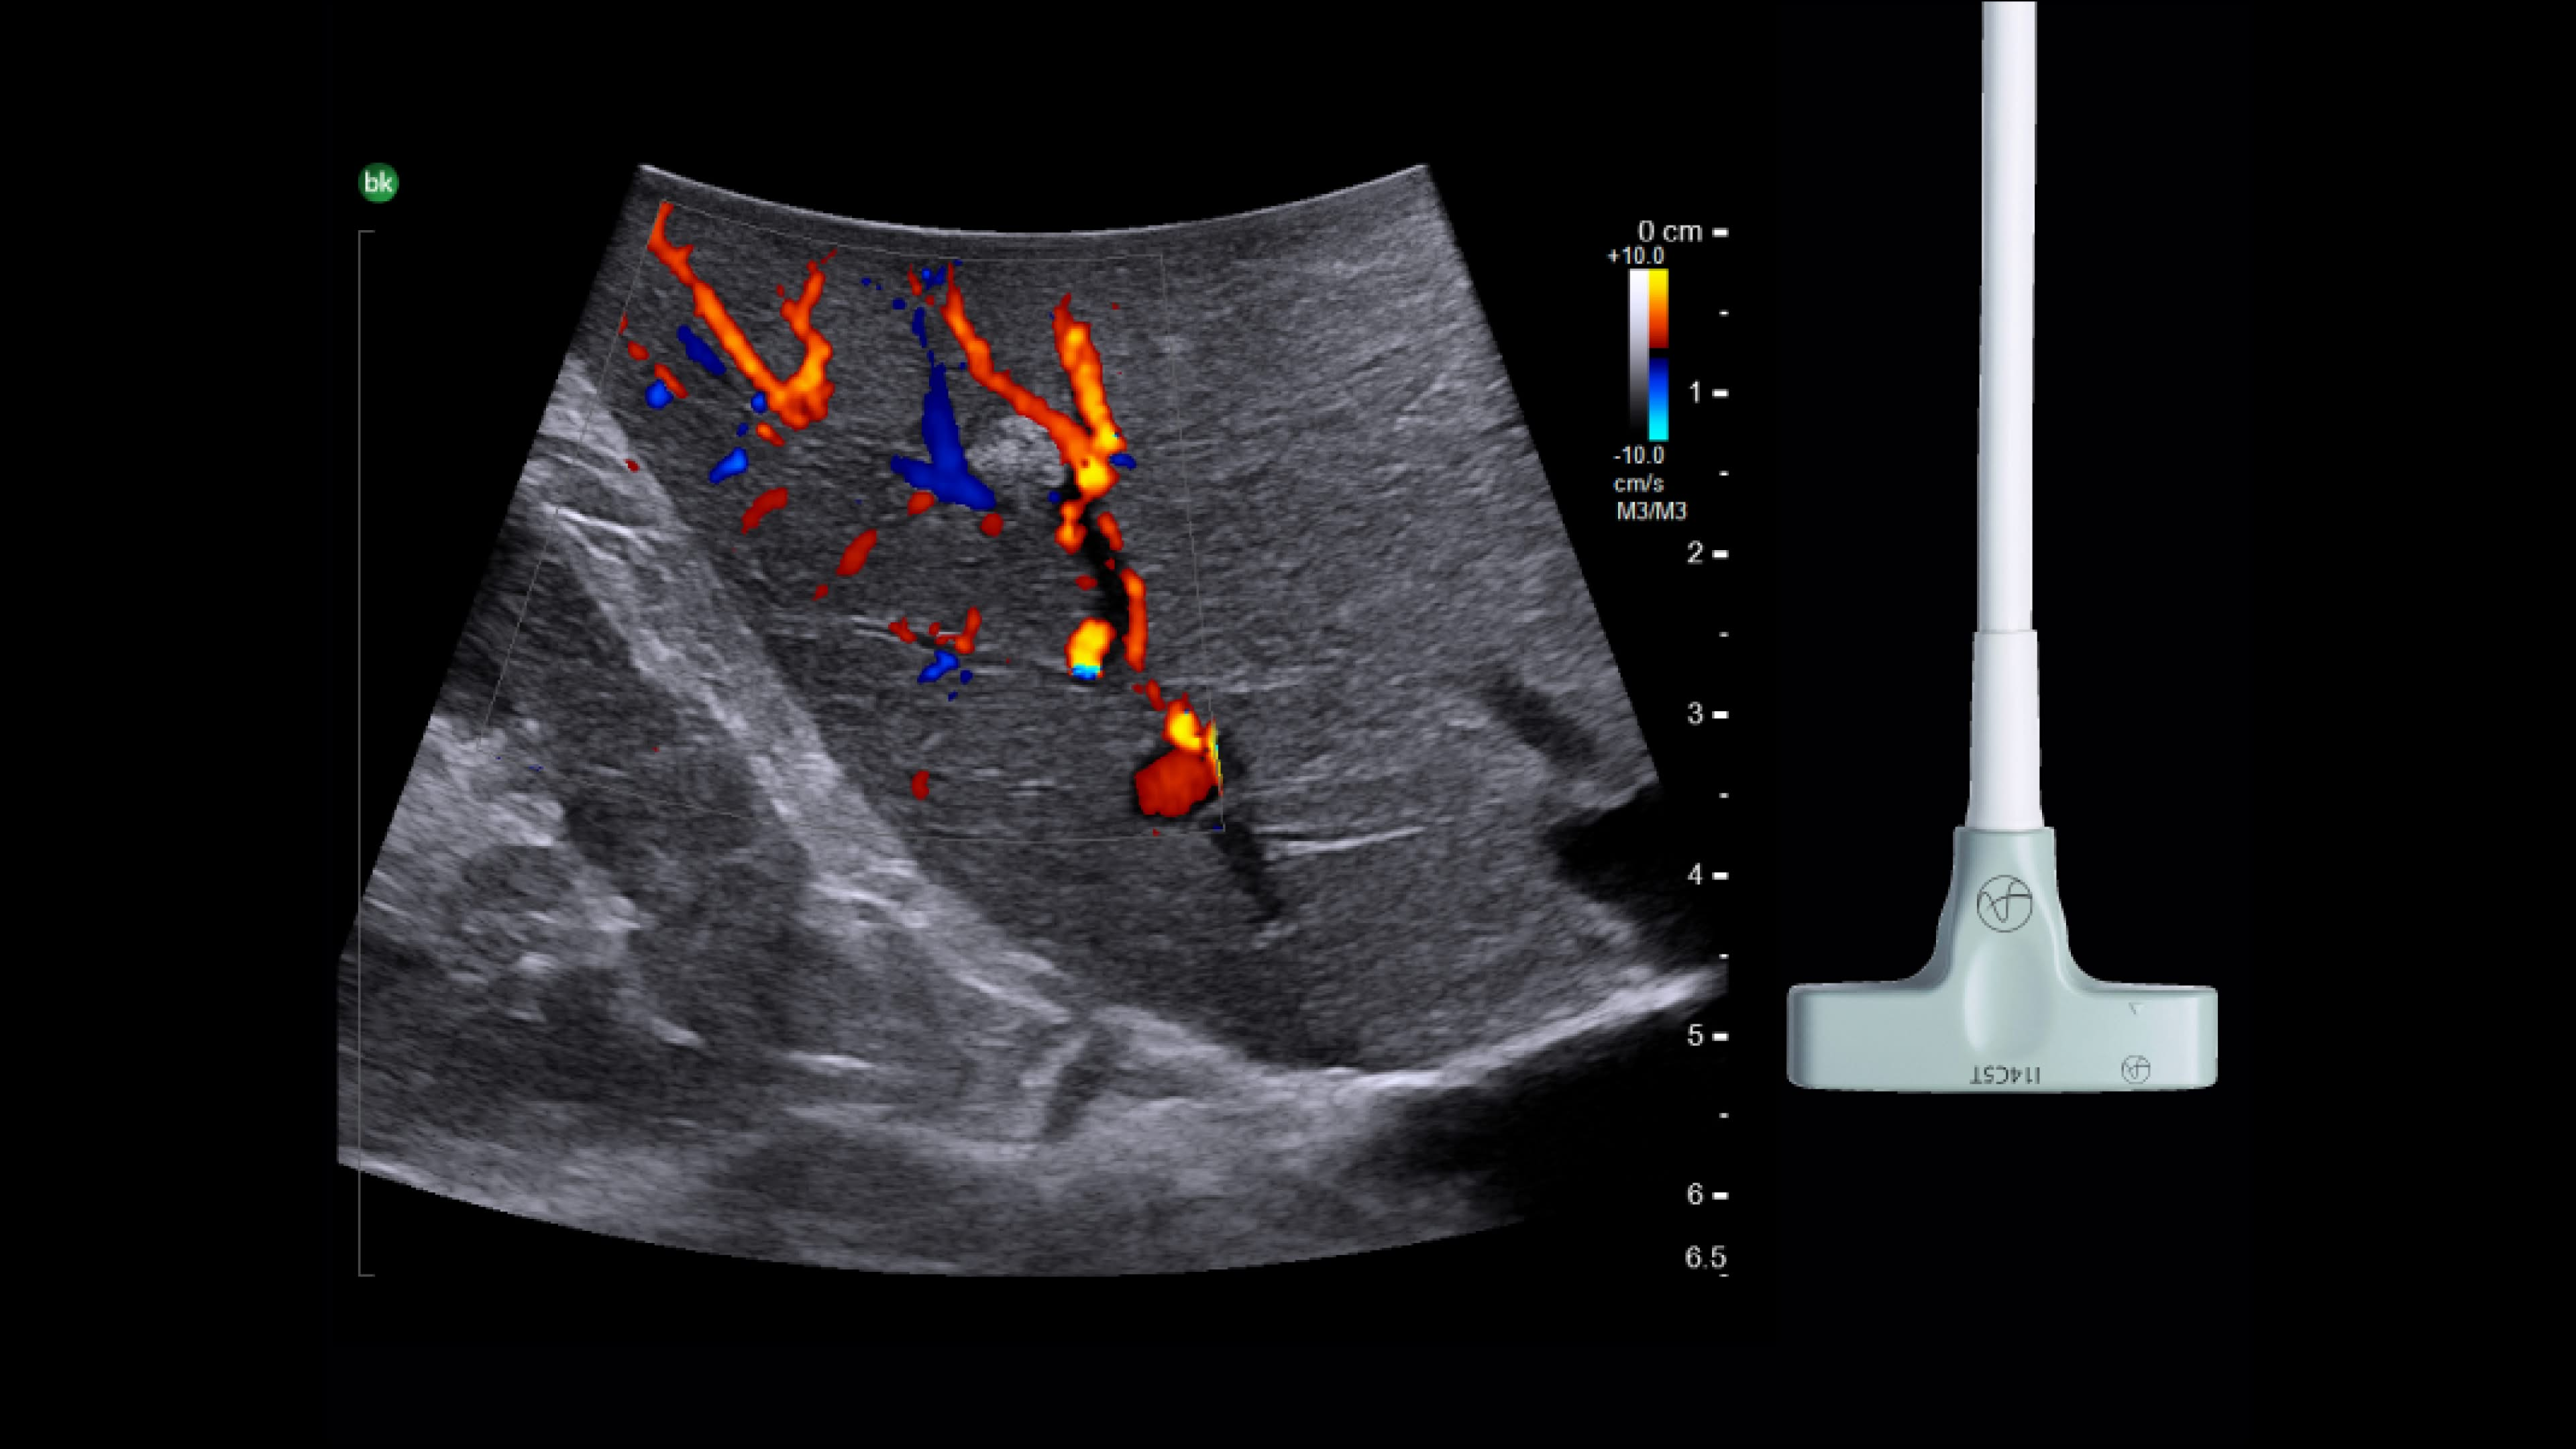

Active imaging with real-time intraoperative ultrasound supports fast imaging of the biliary system and is non-radiating, helping you reduce radiation hazards to your patients and staff.

Imaging to guide cholecystectomies

Discover the clinical benefits of active imaging with intraoperative ultrasound for laparoscopic cholecystectomy procedures. Using bkActiv and the Advanced Laparoscopic Transducer, surgeons can visualize anatomy and monitor progress as many times as needed during the procedure.

iUS is beneficial for cholecystectomies due to its safety, quick and repeatable imaging capabilities and ability to detect choledocholithiasis and enable visualization of biliary tract anatomy.

• iUS has minimal safety risks as it is non-irradiating and does not required cannulation. ¹⁻³

• iUS can be used dynamically throughout dissection adding minimal time to a cholecystectomy procedure. iUS can also repeated, helping to assess common bile duct integrity at the end of the procedure.¹⁻⁵

• iUS helps differentiate between sludge, stone, polyps, cysts, and tumors when determining if there is a presence of gallstones in the common bile duct.⁵,⁶

• iUS uses color flow doppler to help differentiate between vessels and ducts and is overall effective at imaging difficult cases such as inflammation or fibrosis .¹,⁴⁻⁶